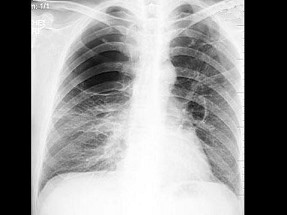

30、单项选择题

男,56岁,胸痛2月余,最近感右臂疼痛、活动受限,胸片如图,最可能的诊断是()

A.右肺癌

B.右上肺不张

C.右肺上沟瘤

D.右侧胸膜肥厚

E.右肺结核